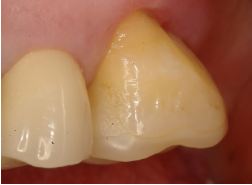

Al momento del examen, 10 (90.9%) EC estaban en función en 10 pacientes. Un molar 26, restaurado con EC, se perdió por enfermedad periodontal después de 12 años y 9 meses en función. Ninguna restauración se desprendió, no hubo recidiva de caries y al examen radiográfico no se observaron lesiones patológicas en los 10 DPET en función (Figs. 1a,1d; 2c; 3c,3d; 4c).

EC en #26 a los 9 años (Gradia).

Control radiográfico a los 9 años